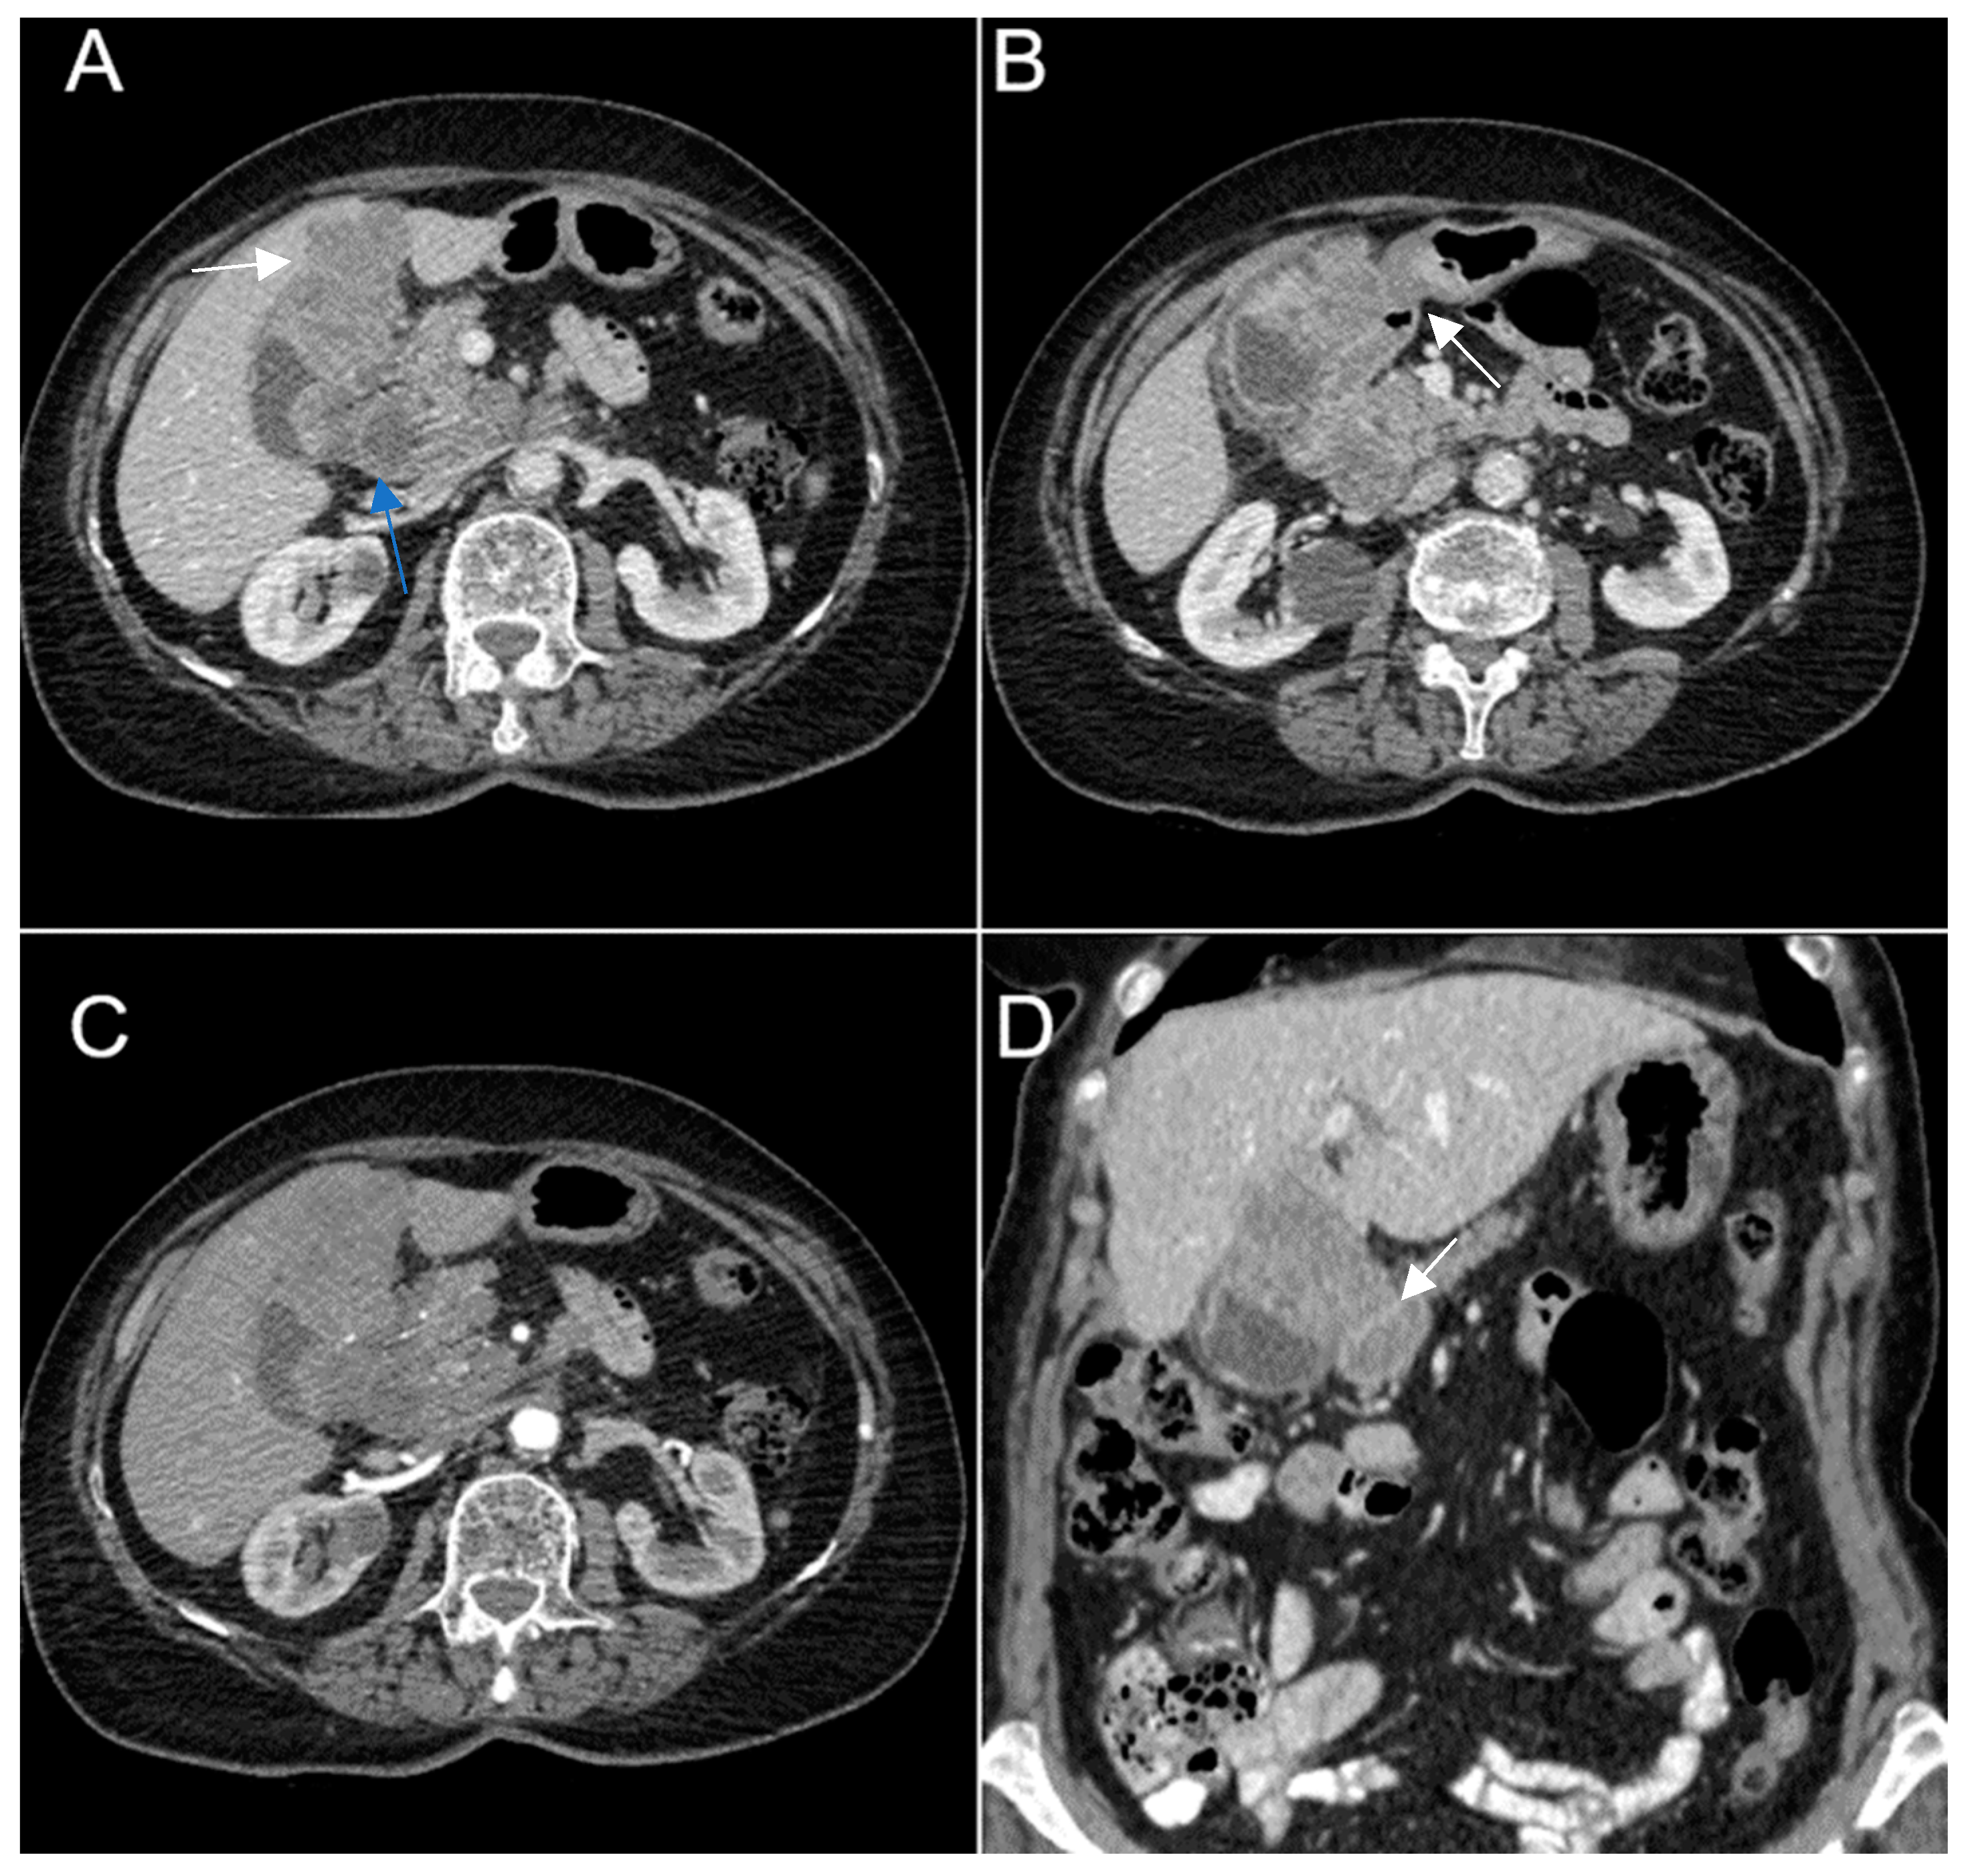

A 67-year-old female patient with a past medical history of hypertension and autoimmune thyroiditis presented to the Emergency Department with abdominal pain accompanied by nausea and weight loss. Physical examinations revealed abdominal tenderness with a palpable mass in the right hypochondrium. Blood sample demonstrated elevated inflammatory markers, hypochromic microcytic anemia, hepatic cytolysis and increased levels of CEA (12.5 ng/mL) and CA 19-9 (51 U/mL). Contrast-enhanced emergency CT (Figure 9) showed a large mass with heterogeneous enhancement, measuring 94/57 mm, that partially replaced the gallbladder and invaded the liver (segment IVb), pyloric antrum and duodenum II. Bulky celiac and mesenteric lymphadenopathies with areas of necrosis, measuring up to 27/25 mm were present.

Figure 9. Multiplanar sections of contrast-enhanced CT acquisitions richly illustrating gallbladder carcinoma. (AD). A large, inhomogeneous pseudonodular mass with heterogeneous contrast enhancement, with invasion in the adjacent liver, pyloric antrum and duodenum II (white arrows). (A) Lymphatic metastases; with compressive effect on the inferior vena cava and right renal artery and vein (blue arrow).